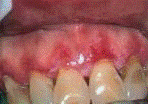

Катаральный стоматит (рис.4, приложение) - распространенное заболевание слизистой оболочки ротовой полости, которое возникает и у детей, и у взрослых. Основная причина возникновения - недостаточная санация ротовой полости, которая приводит к размножению болезнетворных микроорганизмов. Довольно часто катаральный стоматит возникает у тех людей, которые имеют зубной камень, налет, незалеченный кариес. Даже острые края зубов или только что поставленные пломбы могут способствовать возникновению этого заболевания. Часто катаральный стоматит возникает из-за резкого ослабления иммунитета.

Рис.4. Катаральный стоматит.